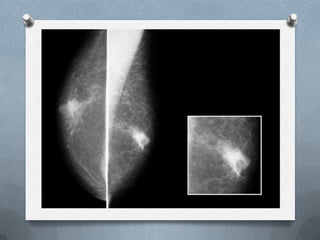

El carcinoma ductal in situ es una neoplasia originada en el epitelio ductal del tejido mamario caracterizada por la proliferación de células epiteliales malignas sin evidencia de invasión. Puede presentarse como comedocarcinoma, cribiforme, papilar o micropapilar según su patología. Generalmente se diagnostica por mamografía al detectar microcalcificaciones, aunque también puede encontrarse de forma incidental o por hallazgos clínicos. Su tratamiento es individualizado e integrado e incluye resección quirúrgica con o